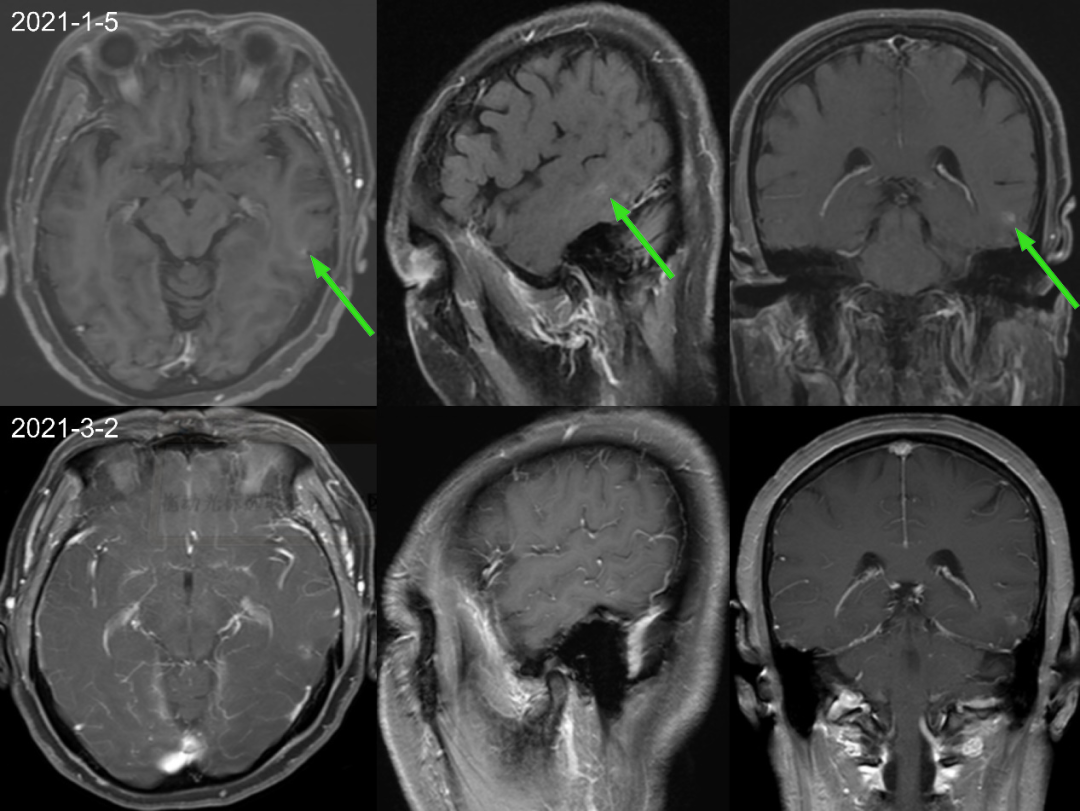

首次检查 2021-1-5 日发现左侧颞叶强化结节,轴矢冠状位都能看到,但是平扫看不到,周围亦未见水肿信号,此时没经验的诊断医生估计会考虑为转移瘤,一直困扰着患者和临床医生。但是在其余 7 次检查中 2021-3-2 至 2022-6-22 一年半多的时间,左侧颞叶强化结节仍然存在,并且基本没啥变化,如果是转移瘤会这么长时间无任何干预都处于一个静止状态吗?,此时是不是需要考虑其他的诊断?,究竟是什么呢,有经验的医生肯定会想到:是毛细血管扩张症。

仔细观察本例左侧颞叶强化结节,中心为明显强化,周围为稍淡淡样的强化,此为毛细血管扩张症的特点。